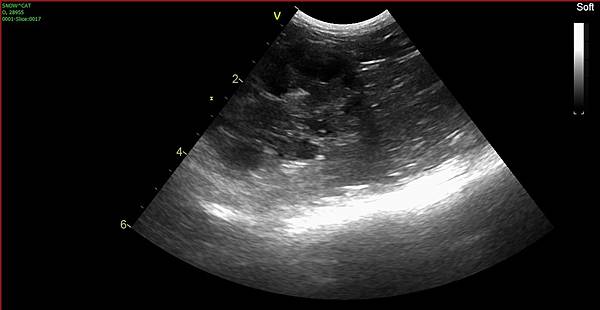

他的膀胱狀況非常好

超音波底下只有一點點,幾乎是沒有尿沙

今天抽尿送驗沒有細菌的話,就能停掉處方飼料和保健品了